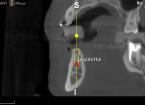

Progettazione virtuale / chirurgia guidata Un esempio della progettazione 3D di un intervento di posizionamento implantare SENZA BISTURI. Photogallery: